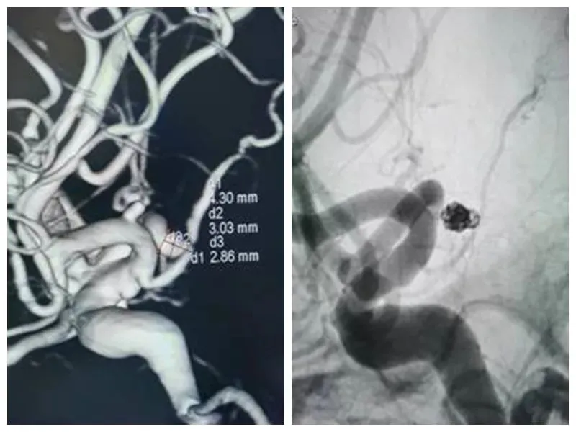

一、技術能力:收治所有神經係(xì)統疾病,目前常規診(zhěn)治的疾病有:腦梗死、腦出血、蛛網膜下腔出血、慢性腦供血不足、頭暈(yūn)、頭痛、三叉神經痛及中樞神經係(xì)統感染(各種(zhǒng)腦炎)、癲癇、帕金森病、周圍神經病(bìng)、老年癡呆(dāi)、失(shī)眠(mián)等各種神經係統疾病。二、科室特色:在2007年創先開展急性腦梗超(chāo)早期溶栓治療(liáo)並取得可喜成果,不少生(shēng)命垂危的病人經積極溶栓治療後(hòu)得到較好的治療(liáo)效果,對急性腦出(chū)血的處理(lǐ)上也有獨到的經驗。在2018年(nián)成立卒中中心,由(yóu)多學(xué)科聯合組(zǔ)成的腦血管病診斷治療快速反應小組,為急性腦血管(guǎn)疾病患者開通了綠色通道,為腦血管疾病患(huàn)者治療爭取寶(bǎo)貴時間。2019年12月順利通過國家級卒中中心評審。2020年引進(jìn)數字減影血管造影X線機,內二科(kē)已常規開展腦血管造影,腦梗死取栓,顱內動脈瘤填(tián)塞(sāi),腦血管支架植入等手術。

三、主要設備:數字減影血管造影(DSA)、1.5T雙引擎磁共振、320排CT、數字減(jiǎn)影血管造影X線機、常規(guī)腦電圖、24小時動態腦電圖、肌電圖、誘發電位(wèi),經顱多普勒(TCD)、腦脊液檢查、基因檢測等。四、科室電話:0792-2779527(內線5197)